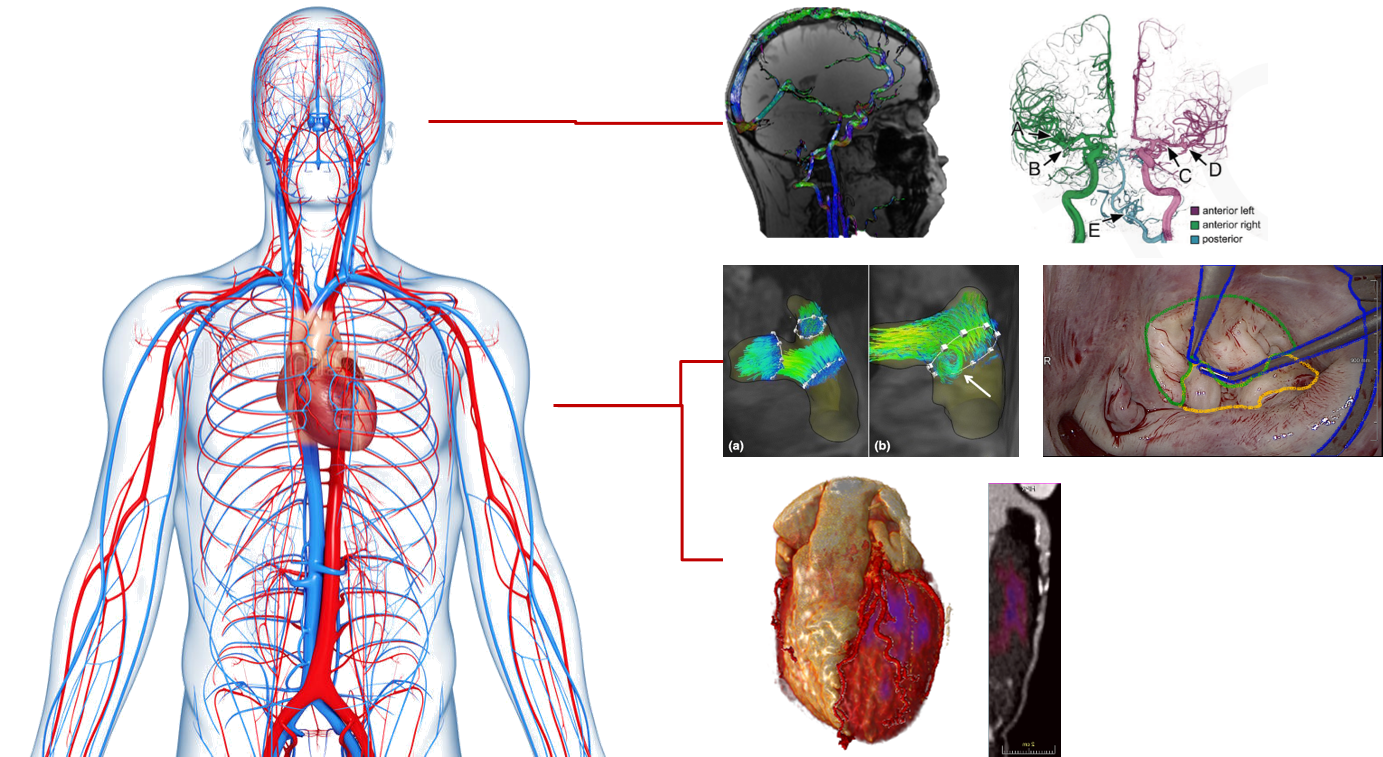

The lecture will introduce typical problems and approaches related to the extraction of information from medical image data. The relevant algorithmic approaches will be theoretically explained. Participants are expected to rehearse the content after class in preparation for the exercises.